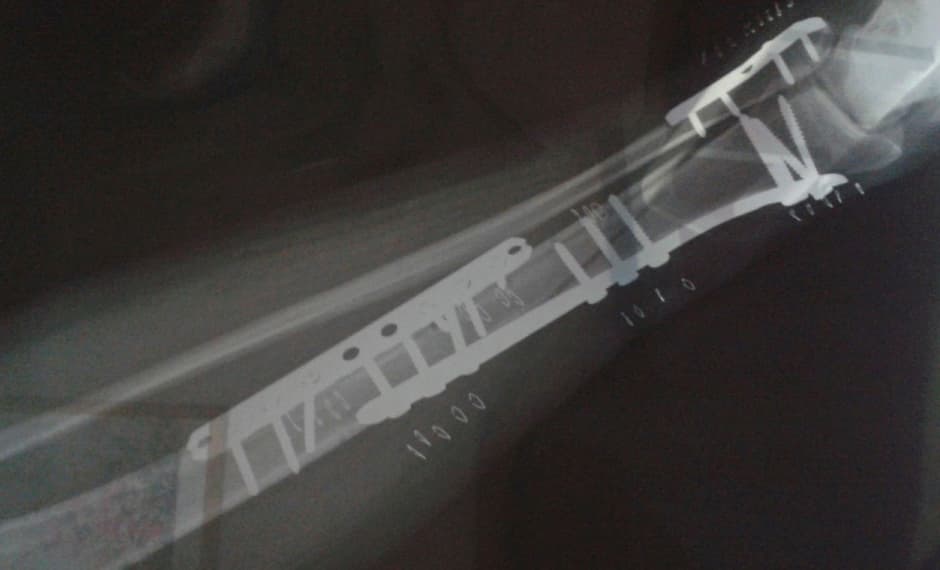

El doctor que me atendía no podía creer que la herida me la hubiera hecho al estar parada. Me había roto la tibia y el peroné y había que operar. Esa noche fue la peor de mi vida, no podía del dolor. Al día siguiente me operaron sin anestesia general.

En total tengo 28 clavos y 2 barritas de metal, una a cada lado del tobillo. Estuve de incapacidad tres meses (de los cuales dos los pasé en cama). Durante 24 días me inyectaron anticoagulantes. Un mes lo pasé en silla de ruedas, tres semanas con andadera y uno más con bastón.